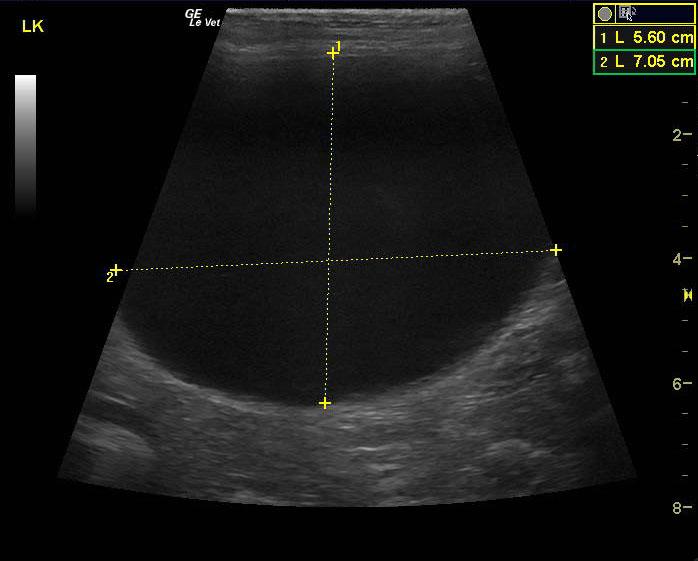

A 15 year old spayed female DMH cat was presented for progressive disease over a 6-8 month period, characterized by poor coat quality, decreased mobility, reduced activity, and pruritic skin lesions that have not responded to antibiotics and use of an E-collar. Abnormalities on physical examination were alopecia, hyperpigmentation, and thinning of the skin of the ventrum, and a non-healing, plaque-like, superficial skin lesion on the cranial aspect of the left stifle and accessory pad of the left carpus. Skin biopsies were scheduled. On urinalysis an inappropriate SG and proteinuria was present with a urine protein: creatinine ratio of 0.3. Abnormalities on serum biochemistry included hypercalcemia and hyperproteinemia. Radiographs showed arthritis of elbow, LS junction, and hips, as well as a mass in the region of the left kidney.